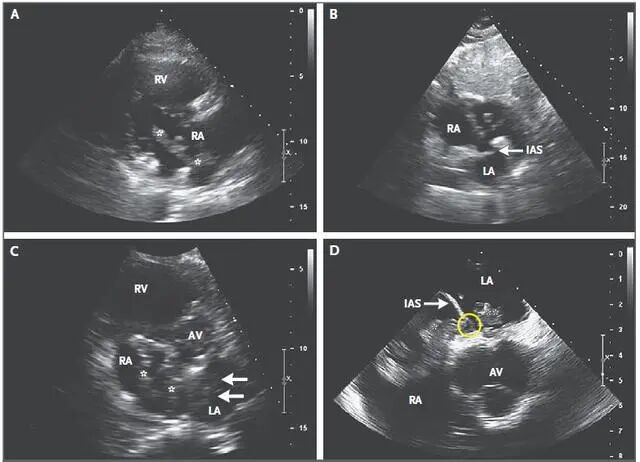

心脏超声是利用超声波检查心脏内部的结构,主要检查心脏的器质性疾病,属于超声医学的范畴。心脏彩超主要检查心脏的形态学有没有异常,心功能是否正常,特别对先天性心脏病是首选的检查方法,心脏彩超是唯一能动态显示心腔的内结构,心脏的搏动和血液流动的检查,对人体没有任何损伤。

心脏探头就像摄像机的镜头,将探头放在胸前来回移动,随着探头的转动,心脏的各个结构清晰地显示在屏幕上。